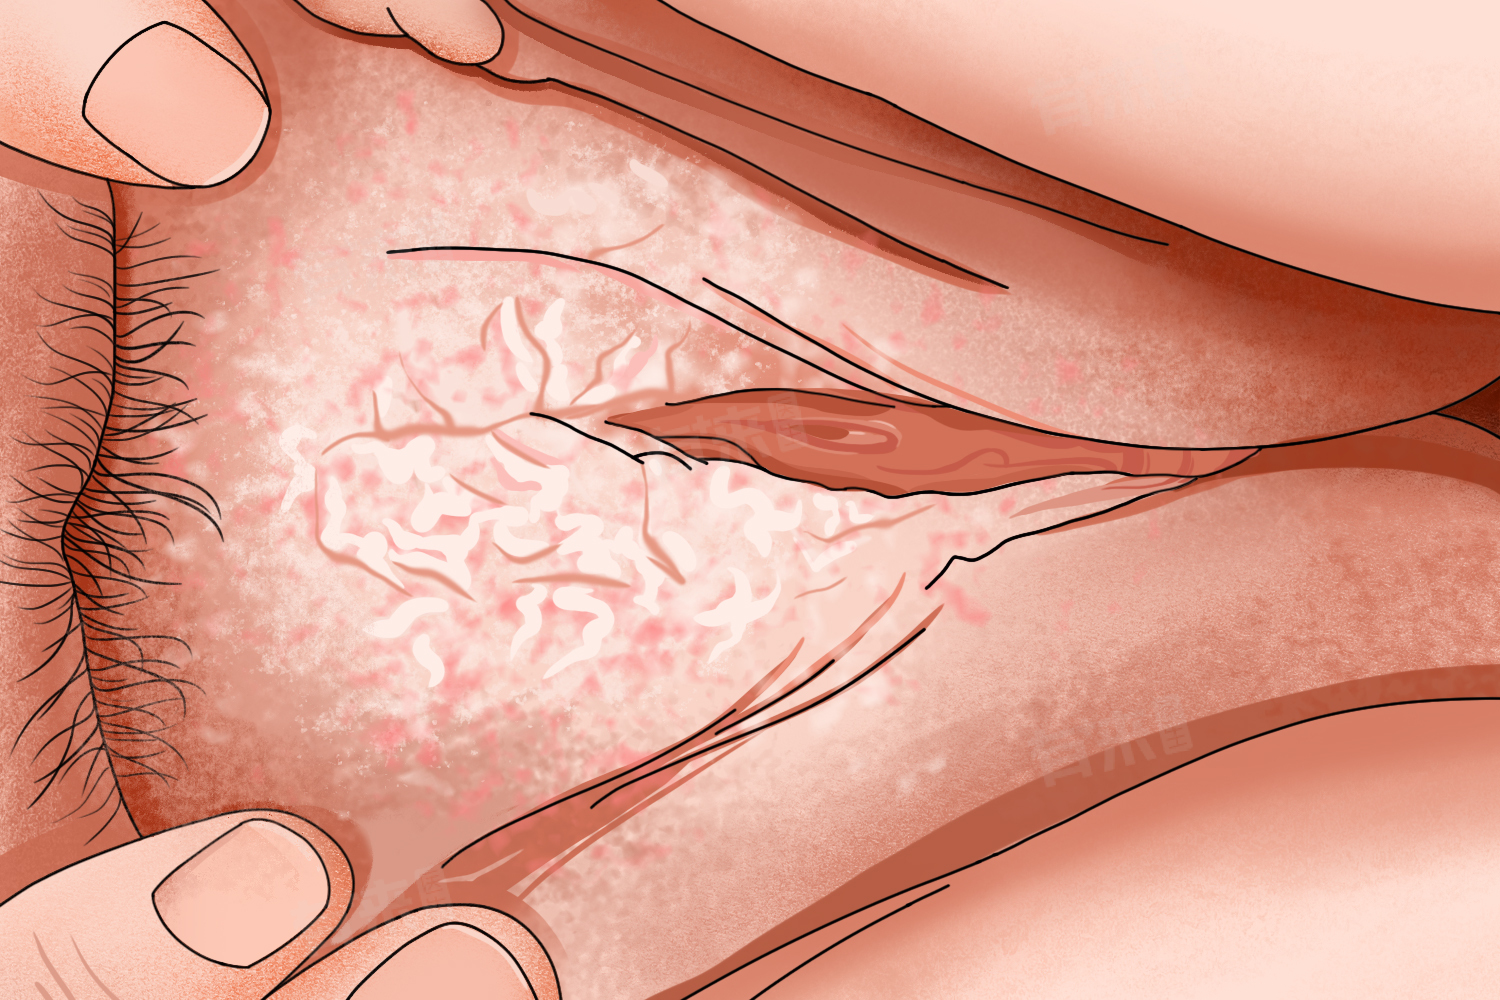

女性私密部位出现白色的情况可能有多种原因,可能是阴道炎、外阴白癜风、维生素缺乏等,可以通过调整饮食、使用抗真菌药物、光疗等方法来治疗。

2、阴道炎:尤其是外阴阴道假丝酵母菌病,也就是常说的霉菌性阴道炎,会导致阴道分泌物增多,呈豆腐渣样或凝乳状,并伴有外阴瘙痒和灼热感。治疗方面,可以遵医嘱使用抗真菌药物,如克霉唑栓剂、制霉菌素栓剂等局部用药,或者口服氟康唑等抗真菌药物进行治疗。

3、外阴白癜风:这是一种由于黑色素细胞被破坏而引起的疾病,可能导致外阴皮肤变白,同时可能伴有身体其他部位的皮肤变白。这种情况下,需要在医生的指导下进行综合治疗,包括药物治疗、光疗等。